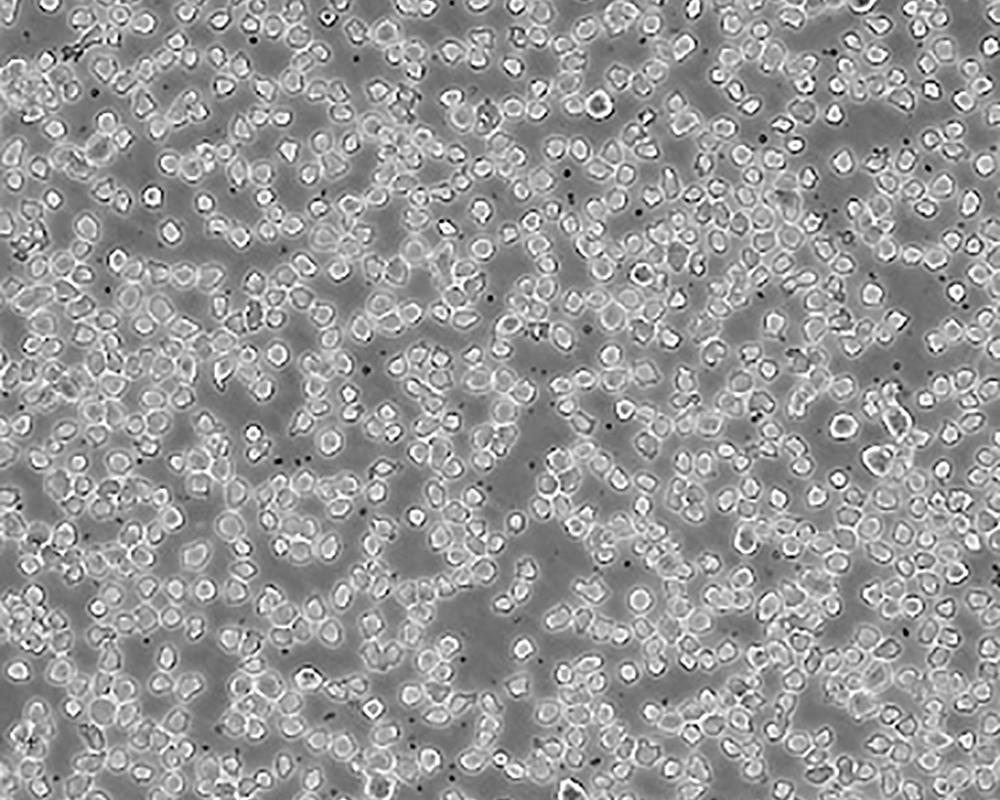

THP-1

產(chǎn)品名稱 THP-1

中文名稱 人單核細(xì)胞白血病

組織來源 急性單核細(xì)胞白血病;男性

生長特性 suspension

形態(tài)特征 monocyte

細(xì)胞描述 該細(xì)胞從一名1歲的患有急性單核細(xì)胞性白血病的男孩的外周血中分離建立。該細(xì)胞可以吞噬乳膠顆粒和激活的紅細(xì)胞,細(xì)胞膜和胞漿內(nèi)均沒有免疫球蛋白,表達C3R和FcR;可受佛波酯TPA誘導(dǎo)向單核系方向分化;可作為轉(zhuǎn)染宿主。